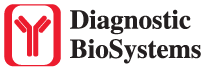

This MAb recognizes human 17-26kDa protein, which is identified as cytokine TNF-α (Tumor Necrosis Factor-alpha). Monomeric human TNF-α is a 157 amino acid protein (non-glycosylated) with a reported molecular weight of 17 kDa and can be expressed as a free molecule, also TNF-α is generated as a precursor form called transmembrane TNF-α can be expressed as a cell surface type II polypeptide consisting of 233 amino acid residues molecular weight 26 kDa. TNF-α is an important cell-signaling component of the immune system. It is a protein secreted by LPS stimulated macrophages, and causes tumor necrosis when injected into tumor bearing mice. TNF-α is currently being evaluated in treatment of certain cancers and AIDS Related Complex.

| Cellular Localization | Cytoplasmic and extracellular (secreted) |

| Positive Control Tissue | Colon, Histiocytoma, Pancreas |